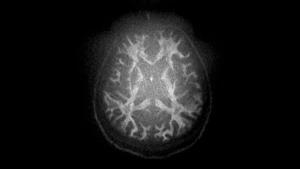

MAGNETOM Cima.Xによる拡散強調画像 |

同社従来機(MAGNETOM Prisma)による拡散強調画像 |